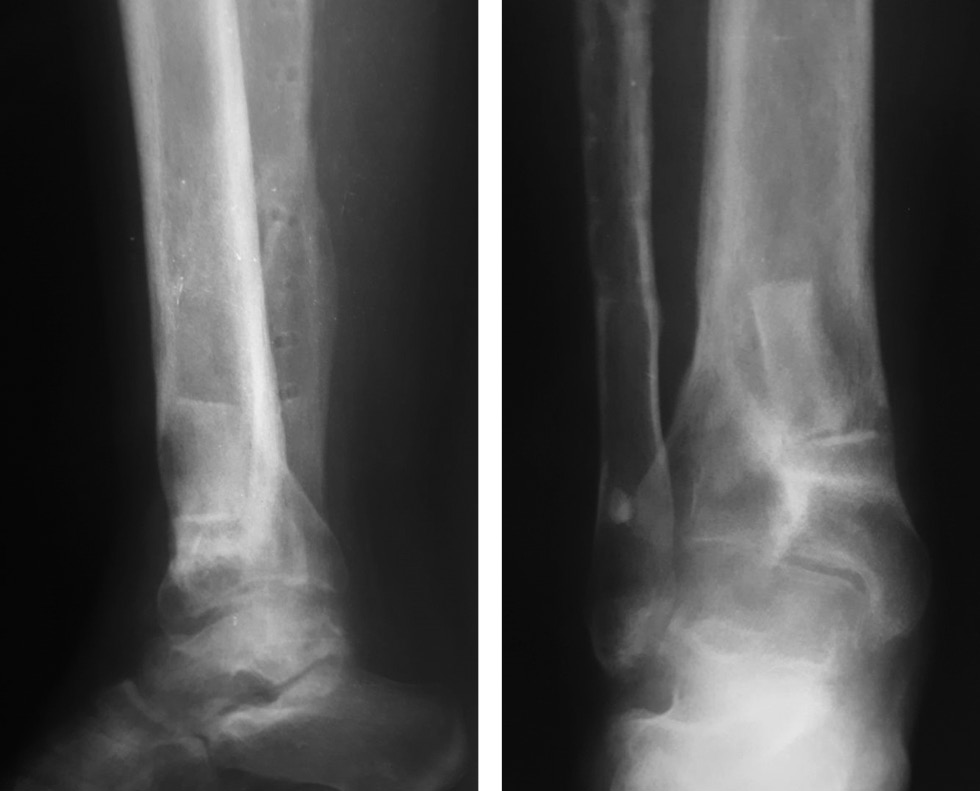

Considering the course of chronic osteomyelitis, complicated by a fistulous process with trophic changes in soft tissues, radical reconstructive intervention was decided, which included the removal of the hardware of the right fibula, fistulectomy of the lower third of the right tibia, osteonecrectomy of the distal metaphysis of the right tibia, bone autografting of the defect (iliac crest), plastic surgery of a wound defect using an islet dorsal foot graft with axial blood flow, and plastic surgery of the donor wound with a split skin graft (Fig. 5). Histological examination revealed chronic nonspecific inflammation with exacerbation, and bacteriological examination revealed S. aureus 103 with high sensitivity. The patient received a course of antibacterial therapy with cefazolin at an age-appropriate dose. In dynamics, the infectious and inflammatory process stopped. Control radiographs after 6 months showed the integration of bone grafts (Fig. 6). The support ability of the limb has been restored; when walking >1.5 km, she experienced pain (up to 3 points on the visual analog scale) in the ankle joint. The shortening did not increase during the follow-up period.

Fig. 6. Control radiographs after 6 months and integration of bone grafts without signs of an infectious–destructive process